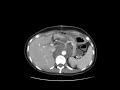

Retroperitoneal Ganglioneuroma

MRI and CT images demonstrate a poorly marginated soft tissue massin the retrioperitonuem surrounding the celiac and SMA with no appreciable vascular narrowing or attenuation. This was found to be a retroperitoneal ganglioneuroma.